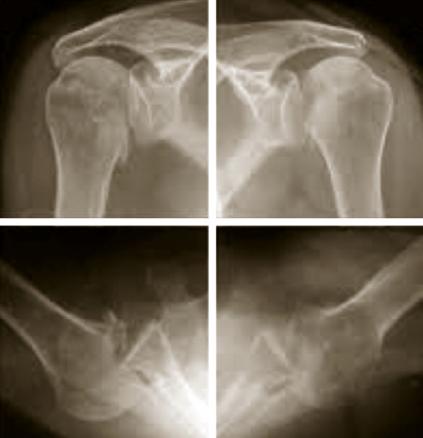

Luxation gléno-humérale postérieure bilatérale

Suite à une crise d'épilepsie.